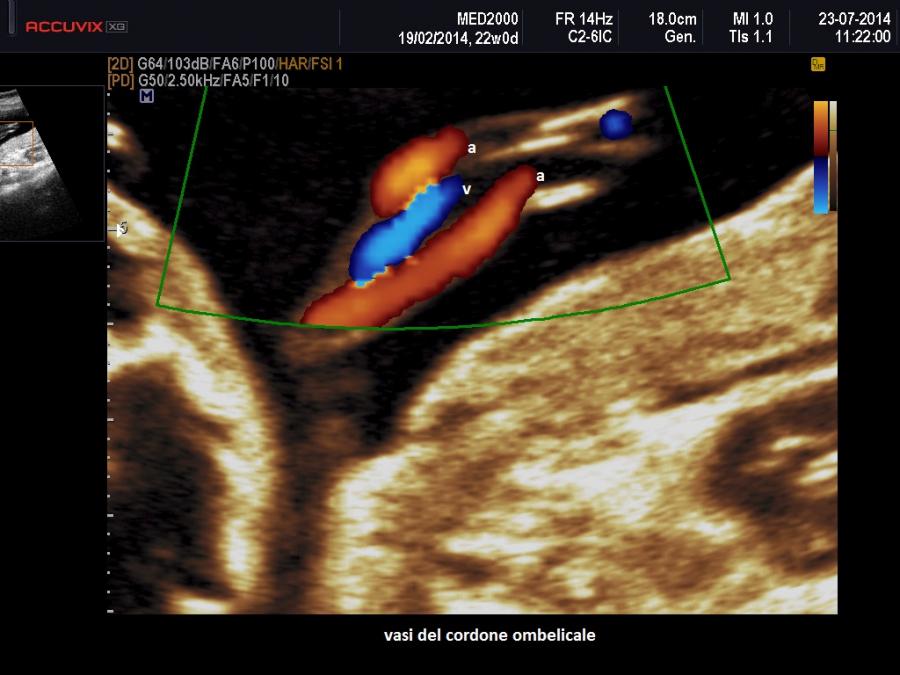

Il cordone ombelicale presenta normalmente tre vasi: una vena e due arterie, destra e sinistra. L'Arteria ombelicale singola (SUA) è una anomalia del sistema vascolare del feto in cui manca una delle due arterie.

Note di embriologia: negli stadi precoci della vita intrauterina i vasi del cordone sono 4, due vene e due arterie; intorno alla sesta settimana di gestazione la vena ombelicale di destra si chiude rimanendo solo la sinistra. Il cordone ombelicale definitivo è quindi formato dalle due arterie ombelicali, destra e sinistra, e dalla vena ombelicale di sinistra.

Il segno ecografico caratteristico è la presenza di due soli vasi nel cordone ombelicale. Al color-Doppler si osserva un solo vaso lateralmente alla vescica. In scansione trasversa si osserva un cordone con due soli vasi. Spesso l'unica arteria presente nel cordone va incontro ad una dilatazione compensatoria e mostra un calibro superiore ai 4 mm.; anche gli indici di resistenza risultano al di sotto della media per l'epoca gestazionale.